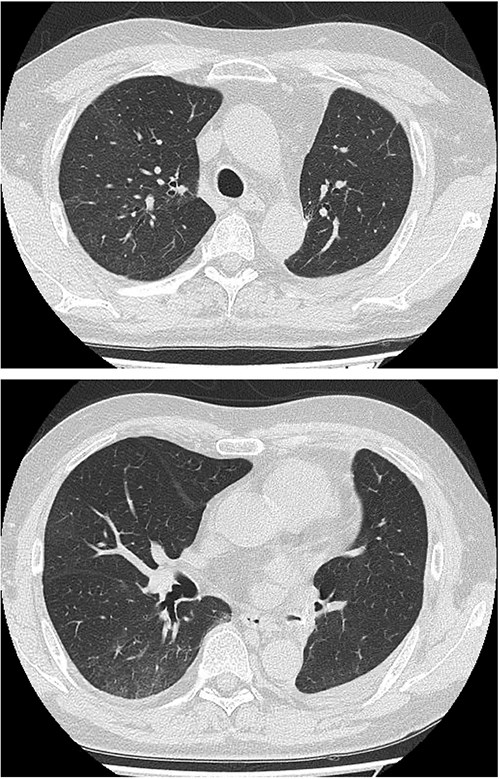

Serial chest imaging demonstrating pulmonary complications. (a) Postoperative day (POD) 10: Initial presentation without significant abnormalities. (b) POD 16: Peripheral ground-glass opacities (arrowheads). (c) POD 27: Patchy consolidation (solid arrows) with new ground-glass opacities and pleural effusion (open arrows). (d) POD 36: Progressive consolidation (solid arrows).

On POD 27, he was readmitted with fever (38.2°C) and respiratory failure. COVID-19 testing was negative. Chest computed tomography revealed patchy consolidations mixed with ground-glass opacities in the right upper lobe with notable expansion, and new ground-glass opacities in the right middle lobe and residual left upper lobe periphery (Fig. 2c). Findings excluded recurrent air leak or aspiration pneumonia. Despite antibiotic therapy, oxygen requirements increased to 2 L by POD 29.

Methylprednisolone pulse therapy (1 g/day for 3 days) was initially administered, followed by oral prednisolone (30 mg). However, oxygen requirements increased to 4 L on POD 31 (Fig. 3). On POD 36, a second methylprednisolone pulse course was initiated with cyclosporine A (150 mg) owing to progressive consolidation on chest imaging (Fig. 2d). Oxygen support was discontinued by POD 38, and he was discharged on POD 52. Follow-up image on POD 104 showed substantial radiological improvement (Fig. 4). Immunosuppressive medications were successfully tapered and discontinued by POD 329. This case was diagnosed as delayed-onset OP as a manifestation of post-acute COVID-19 syndrome, characterized by the biphasic clinical course and distinctive radiological progression occurring weeks after acute COVID-19 infection.